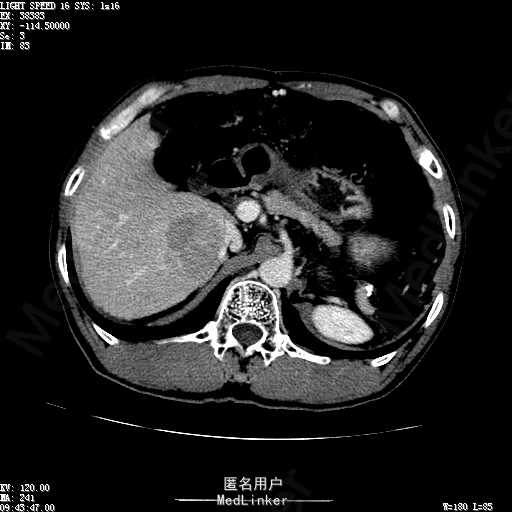

查体:体温36.4℃,脉搏76次/分,呼吸18次/分,血压110/70mmHg。神志清晰,发育正常,营养中等,体位自如,表情安静,慢性病容,检查合作。皮肤粘膜颜色正常,无瘀点、紫癜,有肝掌,无蜘蛛痣,无水肿,毛发的生长与分布正常。浅表淋巴结浅表淋巴结未触及肿大。无巩膜黄染,结膜正常。口唇红润,粘膜正常,舌正常,牙龈正常,扁桃体无肿大,无咽部充血。颈部外形对称,颈静脉正常,肝颈静脉回流征阴性,气管居中。甲状腺正常,无颈部血管杂音。胸部形态正常,呼吸运动平稳规律,无呼吸困难,肋间隙正常。触诊语颤正常,无胸膜摩擦感,肺下界位于右锁骨中线第六肋间。呼吸音正常,未闻及干湿啰音,无胸膜摩擦音。无心前区隆起,心尖搏动正常,心率:76次/分,心律齐,心音正常,无杂音,无心包摩擦音。无大动脉及周围血管征,无奇脉及交替脉,无水冲脉,无枪击音,腹型对称,无腹壁静脉曲张,未见胃肠型及蠕动波,无瘢痕,脐部正常。无压痛,无反跳痛,无腹肌紧张,无腹部包块。肝未触及,Murphy征阴性,脾未触及,肾未触及,无移动性浊音。无肝区叩击痛,无肾区叩击痛,无脾区叩击痛。肠鸣音正常4次/分,无气过水声。外阴及肛门:未查。四肢正常,关节正常,无下肢水肿,无下肢静脉曲张,无杵状指趾。 辅助检查:彩超:肝表面欠光滑,肝内占位5.2*5厘米 ct如下图

诊断:乙肝肝硬化 代偿期 原发性肝癌。 患者病史明确,目前化验转氨酶轻度升高,说明有活动性肝损伤,白蛋白降低提示肝脏合成代谢功能下降,AFP从一年前至今逐渐升高,提示活性肿瘤细胞增多。CT所见明确诊断肝癌,并有周围卫星灶,应近期行TACE治疗。 处置:DSA下肝动脉造影及TACE 手术简要经过:患者平卧位,术区皮肤消毒,铺手术巾,2%利多卡因局麻后,Seldinger法穿刺右股动脉,入血管鞘,5F猪尾管腹主动脉造影,超滑导丝yidao5F RH管腹腔干、肠系膜上动脉、左肾动脉分别造影,腹腔干造影时,见肝右叶7-8处小结节样肿瘤染色,未见外凸生长较大病灶染色。微导管超选肝右动脉注入三氧化二砷碘油混悬液10毫升,横结肠遮挡部位见较大病灶有伞状碘油沉积。复查造影未在见肿瘤染色,拔出导管和血管鞘,穿刺处压迫止血,加压包扎。术毕。

患者术后8天来,无不适,无发热,无腹痛和腹胀,无恶心呕吐,食欲睡眠好,尿便正常。 查体:神志清,巩膜无黄染,心肺听诊无异常,腹软,无压痛,肝脾肋下未触及,移动性浊音阴性,双下肢无浮肿。 复查化验结果:丙氨酸氨基转移酶 116 U/L、天门冬氨酸氨基转移酶 41 U/L、胆碱酯酶 1995 U/L↓、总蛋白 56.3 g/L、白蛋白 25.9 g/L。白细胞计数 5.8 10^9/L、红细胞计数 3.18 10^12/L、血小板计数 175.0 10^9/L、*血红蛋白 83 g/L、血小板分布宽度 15.7 、血小板压积 0.175 %、*红细胞压积 24.6 %、平均红细胞血红蛋白 26.1 pg、平均红细胞血红蛋白浓度 337.0 g/L、平均红细胞体积 77.5 fL、平均血小板体积 10.0 fL、嗜碱性粒细胞百分比 0.4 %、嗜碱性粒细胞数量 0.02 10^9/L、中性粒细胞百分比 70.4 %、中性粒细胞数量 4.10 10^9/L、嗜酸性粒细百分比 2.1 %、嗜酸性粒细胞数量 0.12 10^9/L、单核细胞百分比 12.2 %、单核细胞计数 0.7 10^9/L、淋巴细胞数量百分比 14.9 %、淋巴细胞计数 0.9 10^9/L。甲胎蛋白 23564.00 ng/mL 患者术后第8天开始行FOLFOX6化疗。CT上可见明显碘油沉积,术后甲胎蛋白下降治疗有效。嘱患者术后必须定期复查